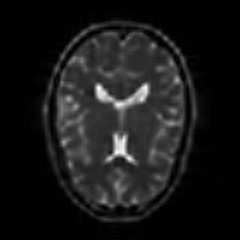

Limited by imaging systems, the reconstruction of Magnetic Resonance Imaging (MRI) images from partial measurement is essential to medical imaging research. Benefiting from the diverse and complementary information of multi-contrast MR images in different imaging modalities, multi-contrast Super-Resolution (SR) reconstruction is promising to yield SR images with higher quality. In the medical scenario, to fully visualize the lesion, radiologists are accustomed to zooming the MR images at arbitrary scales rather than using a fixed scale, as used by most MRI SR methods. In addition, existing multi-contrast MRI SR methods often require a fixed resolution for the reference image, which makes acquiring reference images difficult and imposes limitations on arbitrary scale SR tasks. To address these issues, we proposed an implicit neural representations based dual-arbitrary multi-contrast MRI super-resolution method, called Dual-ArbNet. First, we decouple the resolution of the target and reference images by a feature encoder, enabling the network to input target and reference images at arbitrary scales. Then, an implicit fusion decoder fuses the multi-contrast features and uses an Implicit Decoding Function~(IDF) to obtain the final MRI SR results. Furthermore, we introduce a curriculum learning strategy to train our network, which improves the generalization and performance of our Dual-ArbNet. Extensive experiments in two public MRI datasets demonstrate that our method outperforms state-of-the-art approaches under different scale factors and has great potential in clinical practice.